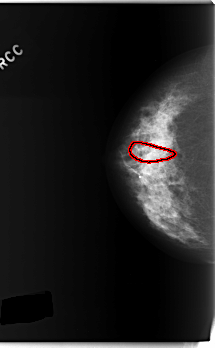

C_0232_1.RIGHT_CC

RIGHT_CC LINES 5904 PIXELS_PER_LINE 3640 BITS_PER_PIXEL 12 RESOLUTION 50 OVERLAY

FILE: C_0232_1.RIGHT_CC.OVERLAY

TOTAL_ABNORMALITIES 1

ABNORMALITY 1

LESION_TYPE CALCIFICATION TYPE FINE_LINEAR_BRANCHING DISTRIBUTION SEGMENTAL

ASSESSMENT 5

SUBTLETY 4

PATHOLOGY MALIGNANT

TOTAL_OUTLINES 1

BOUNDARY